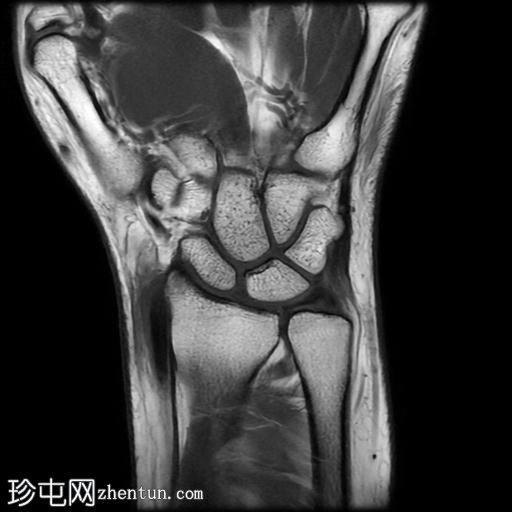

冠状面PD值

脂肪饱和度

冠状面

T2

T1

MRI显示腕部第一背侧肌腱(拇长展肌和拇短伸肌)增厚,并伴有异常增厚的实质内液体信号。腱鞘内液体增多。

尺侧腕伸肌腱可见异常线性实质内液体信号增多,与板状间质撕裂相关。

MRI表现和临床表现提示De Quervain腱鞘炎。